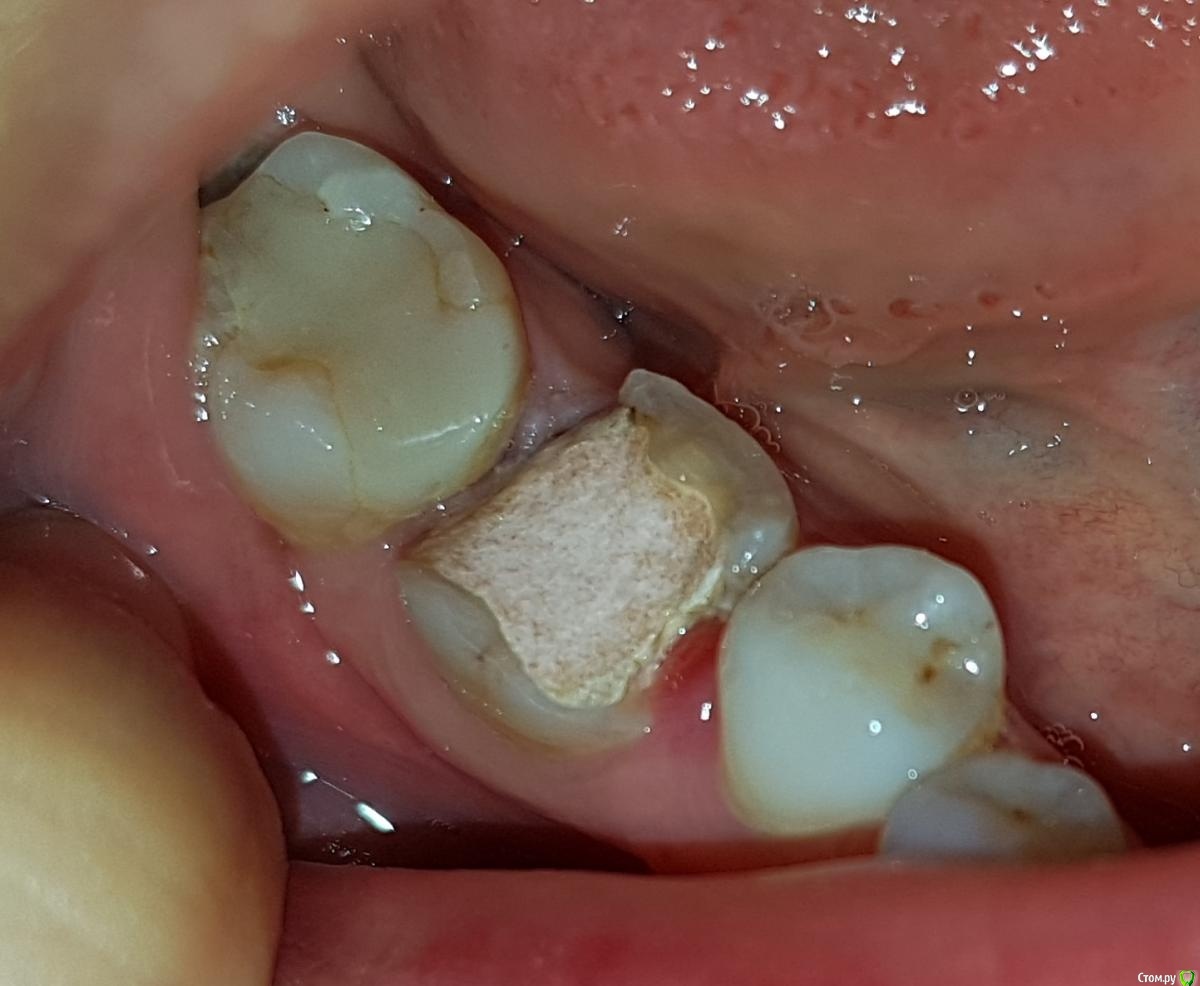

Джастина Опубликовано 2 ноября, 2020 Автор Поделиться Опубликовано 2 ноября, 2020 Это реклама.. Ищите доктора по рекомендациям, а не материал Вот в этом-то и проблема, что никто из знакомых не знает врача, кто бы это делал. Никто не сталкивался. Сейчас этот зуб под временной пломбой, а вчера уже кусочек зуба отвалился. Вот фото: Ссылка на комментарий

St. Опубликовано 2 ноября, 2020 Поделиться Опубликовано 2 ноября, 2020 Зуб разрушен уже достаточно сильно и любая пломба будет стоять на нем не надежно, потому что любой композит в большом объеме плохо выдерживает нагрузку. Соответственно высокий риск повторных сколов пломбы или зуба, плюс в таком объеме очень сложно правильно восстановить анатомическую форму и гладкие выпуклые боковые стенки между зубами чтобы ничего не застревало и было удобно чистить.Лучше рассмотрите вариант керамической накладки\коронки на этот зуб, это дороже но намного долговечнее 3 Ссылка на комментарий